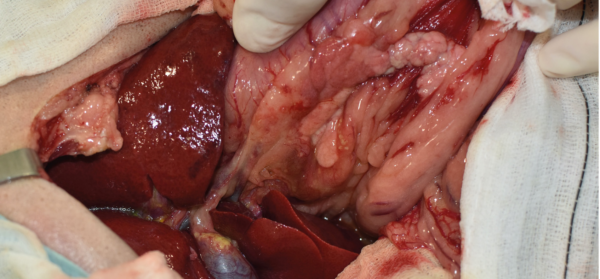

La cirugía de elección es la pancreatectomía parcial y la resección de losnódulos linfáticos (NNLL) centinelas (imágenes 3A-3I). La quimioterapia intracavitaria puede controlar la efusión por carcinomatosis secundaria, pero ofrece una respuesta paliativa de corta duración. La pancreatectomía completa o pancreaticoduodenectomía (técnica de Whipple), descritas en el perro, presentan altas tasas de morbilidad y mortalidad operatorias. La técnica de Billroth II es una opción paliativa a corto plazo en casos de obstrucción intestinal. En un estudio retrospectivo en 34 pacientes felinos con carcinoma pancreático exocrino primario la enfermedad se asoció con una historia previa de diabetes mellitus.35 El carcinoma pancreático exocrino canino se caracteriza por una alta tasa de metástasis y un pronóstico grave general.37

Imágenes 3A – 3I. Secuencia de imágenes quirúrgicas en un perro (con las imágenes del TC), durante una pancreatectomía parcial del lóbulo izquierdo y cuerpo del páncreas, usando un sellador vascular/tisular, por carcinoma pancreático.